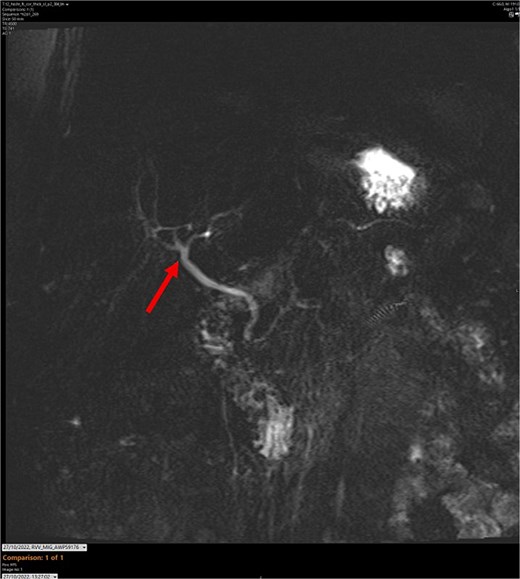

MR maximum intensity projection scan. The arrow points to the largely intact biliary tree. The cystic duct cannot be seen branching from the common bile duct.